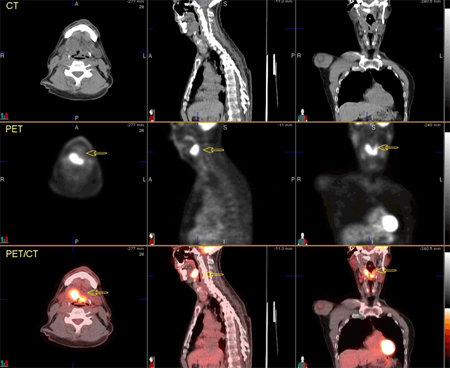

PET-CT fusion scan combines both physiological and anatomical information from PET scan and CT scan, and further improves the accuracy of detecting distant metastases over either modality alone. Accuracy in detecting distant metastases is 94% with PET-CT, 90% with PET alone, and 74% with CT alone.[47] Because most oropharyngeal cancers are treated with radiotherapy to preserve anatomical organs, PET-CT also improves the accuracy of planning radiotherapy treatment.[49] For these reasons, PET-CT is emerging as the preferred modality for staging of oropharyngeal cancer.It can also detect disease recurrence with a greater accuracy (90%) than conventional follow-up with clinical exam, endoscopy, CT, and MRI.[66][67][68] However, it is limited by difficulty distinguishing tumour from infection. It should be repeated 3 months after treatment to avoid false-positive results secondary to inflammation after treatment.[69][Figure caption and citation for the preceding image starts]: 74-year-old man with squamous cell carcinoma of the left tongue base extending into the hypopharynx. Fluorodeoxyglucose PET/CT images demonstrate focal increased metabolic activity in the left hypopharynx/tongue base (arrows)From the collection of Dr Fabio Almeida; used with permission [Citation ends].